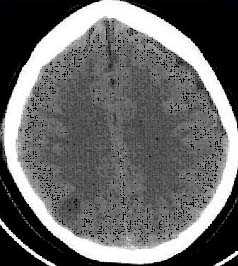

КТ позволяет последовательно изучить мягкие ткани головы, кости черепа, вещество мозга, эпидуральные, субдуральные, субарахноидальные пространства, цистерны основания и желудочки мозга:

- выявить переломы свода и основания черепа (с чувствительностью, намного превышающей традиционную рентгенографию) ,

- выявить наличие внутричерепной гематомы (её характер, локализацию, размеры),

- выявить наличие очага ушиба головного мозга (его локализацию, размеры, характер, наличие геморрагического компонента),

- определить степень сдавления или дислокации головного мозга объемным процессом,

- выявить наличие диффузного или перифокального отека и его степени,

- выявить субарахноидальное кровоизлияние,

- выявить внутрижелудочковую гематому,

- выявить наличие пневмоцефалии.